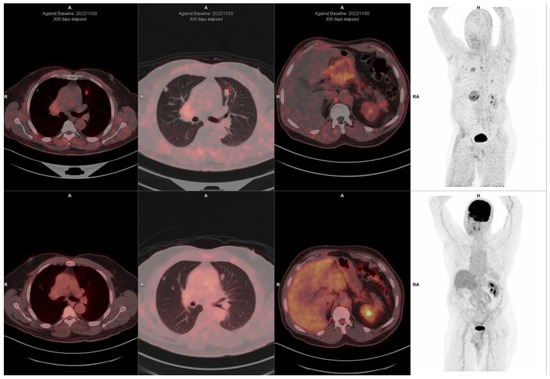

This medical field is constantly seeking innovative solutions to improve diagnostic and treatment using tailored approaches. One such advancement lies in the utilization of novel positron emission tomography (PET) radiotracers. These cutting-edge radiotracers have shown immense potential in revolutionizing medical applications. With the rapid development of medical imaging technologies, PET has emerged as a powerful tool for visualizing and quantifying physiological processes within the human body. Traditional PET radiotracers have been widely used to diagnose and monitor various conditions, including cancer, cardiovascular diseases, and neurological disorders. However, the introduction of novel PET radiotracers has taken medical imaging to new heights.These innovative radiotracers are designed to target specific molecular and cellular processes, allowing for more accurate and precise imaging. By leveraging the unique properties of these radiotracers, medical professionals can gain valuable insight in the molecular mechanisms underlying these diseases. This knowledge facilitates early detection, personalized treatment planning, and therapeutic monitoring.The medical applications of novel PET radiotracers span across multiple disciplines. In oncology, these radiotracers enable the identification of specific tumor markers, aiding in tumor characterization, staging, and treatment response assessment. In cardiology, they can assess myocardial perfusion, monitor metabolism, and identify atherosclerotic plaques. Furthermore, in neurology, novel PET radiotracers facilitate the visualization of neuroreceptors, neurotransmitters, and amyloid plaques, assisting in the diagnosis and management of neurodegenerative disorders.This Special Issue aims to explore the significance and impact of novel PET radiotracers toward various medical applications. It is open to original research and review articles. We look forward to receiving your contributions.